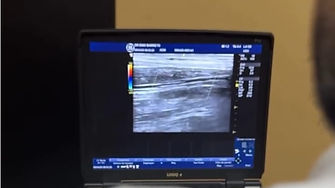

O procedimento consiste na injeção de uma substância esclerosante misturada com ar ou gás, que forma uma espuma densa. Essa espuma é aplicada diretamente dentro da veia comprometida, com o auxílio do ultrassom para visualizar e direcionar corretamente a aplicação. A espuma age promovendo uma reação inflamatória controlada que leva à oclusão da veia tratada. Com o tempo, o organismo reabsorve a veia inutilizada e o sangue é redirecionado para vasos saudáveis.